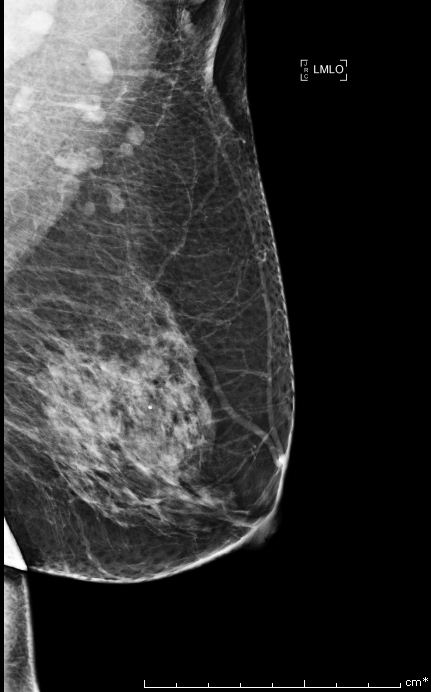

Bi-rads 4 means that the findings on the image are suspicious and that there is an approximately 20 percent to 35 percent chance that a breast cancer is present.

We proceed to calculate the volume of the tumor contained in the breast from the following Bi-rads 4 breast images.

Similarly, we use the same algorithm to evaluate the tumor volume for 4 Bi-rads 4 images and the results are the following:

| Bi-rads 4 Image | Optimal Threshold | Tumor Volume |

|---|---|---|

| Image 1 | 120.574 | 11% of breast volume |

| Image 2 | 59.9143 | 45% of breast volume |

| Image 3 | 239.696 | 0.24% of breast volume |

| Image 4 | 244.590 | 0.0287% of breast volume |